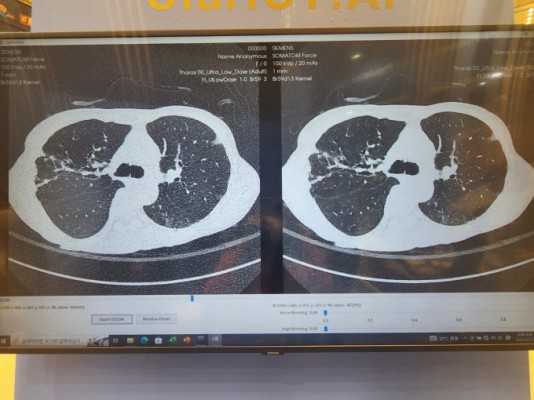

복부 CT(Computed Tomography)는 방사선과 컴퓨터 기술을 결합하여 신체 내부 구조를 3차원으로 시각화하는 영상 진단 방법입니다. 일반적인 X-ray와는 차별화된 측면에서, 복부 CT는 단면 이미지를 연속적으로 수집하여 더욱 정밀한 진단이 가능합니다. 그러므로 의사들은 이를 활용해 매우 다양한 복부 질환을 진단하며, 이를 통해 조기 발견 및 치료 방안을 신속하게 결정할 수 있습니다.

복부 CT 장비는 링 형태의 기계 내부에 방사선 투사 장치와 감지기가 내장되어 있습니다. 환자는 이 링 내부에 누워 있으며, 장비가 부드럽게 회전하면서 단면 이미지를 촬영합니다. 각각의 이미지들은 컴퓨터 소프트웨어에서 합쳐져 3차원의 고해상도 이미지를 생성하게 됩니다. 이러한 과정을 통해 의사는 대장, 간, 췌장, 신장 등 복부 각 장기의 상태를 면밀히 살펴볼 수 있습니다.